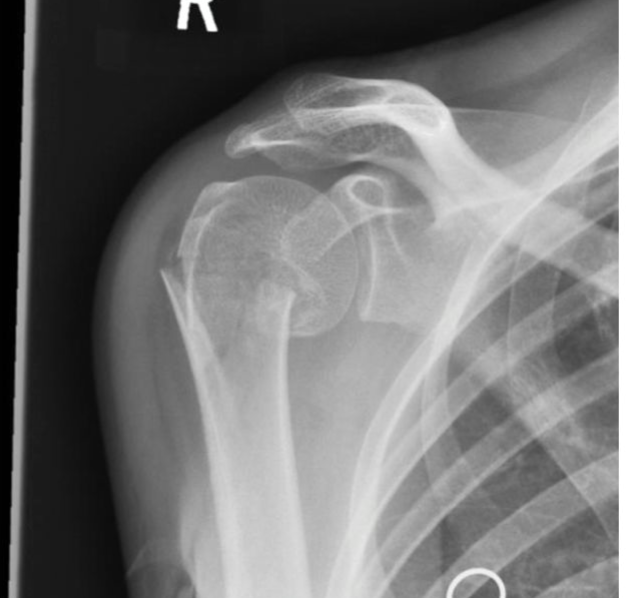

# خلع الكتف وكسر الحديبة الكبيرة: التشخيص والعلاج ## مقدمة حول إصابات الكتف إصابات الكتف شائعة، خاصة بين الرياضيين وا…